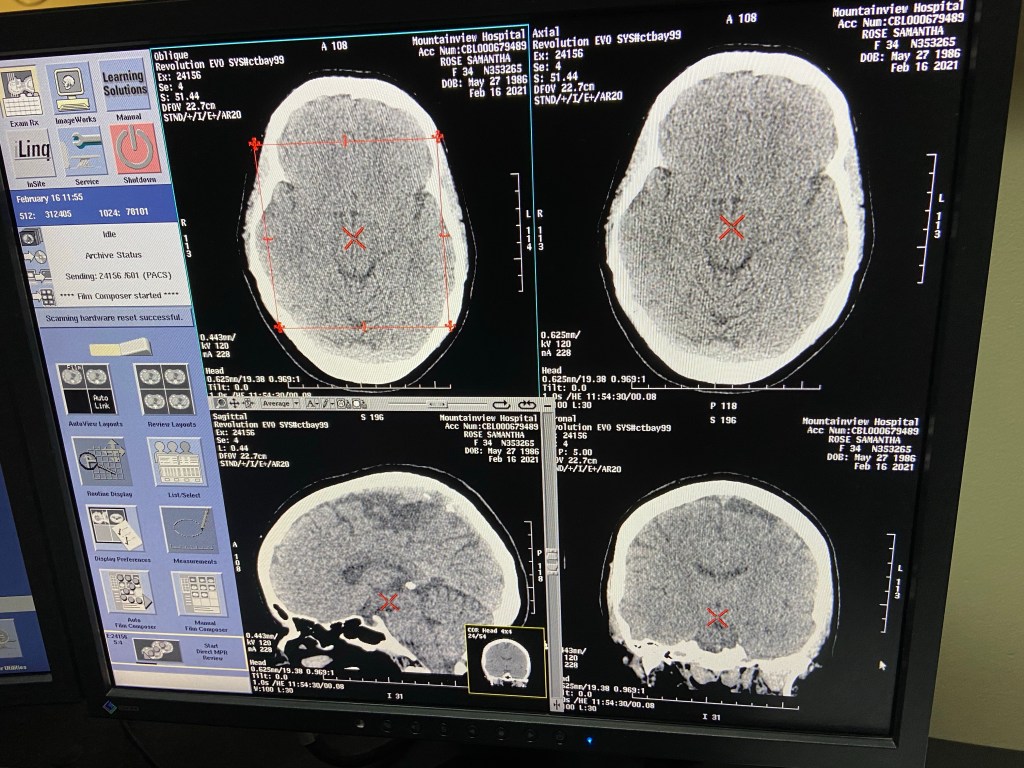

And then, starting that day, I developed a migraine that lasted for three weeks. I couldn’t look at my phone screen or my computer screen for more than a few minutes at a time. I couldn’t be on my feet without feeling like I was going to collapse. I had visual and auditory disturbances. I had to wear sunglasses indoors because the lights inside made me want to die. My doctor made me go to the ER. Nothing showed up on the CT scan. Deep down, I knew nothing would. I told myself and everyone else that it was a cerebral spinal fluid leak and would get mad and defensive when they felt like it wasn’t. I mean, my spinal column has been poked many times (got that spinal tap a few years back!) and I had all of the symptoms and they’re hard to catch in CT scans, and I most definitely didn’t want to believe the migraine was because of this… because something awful was clawing its way to the surface of my mind… I really, really didn’t… but the timing and everything—it’s just hard to ignore. I’ve kinda had to accept it. It is what it is.